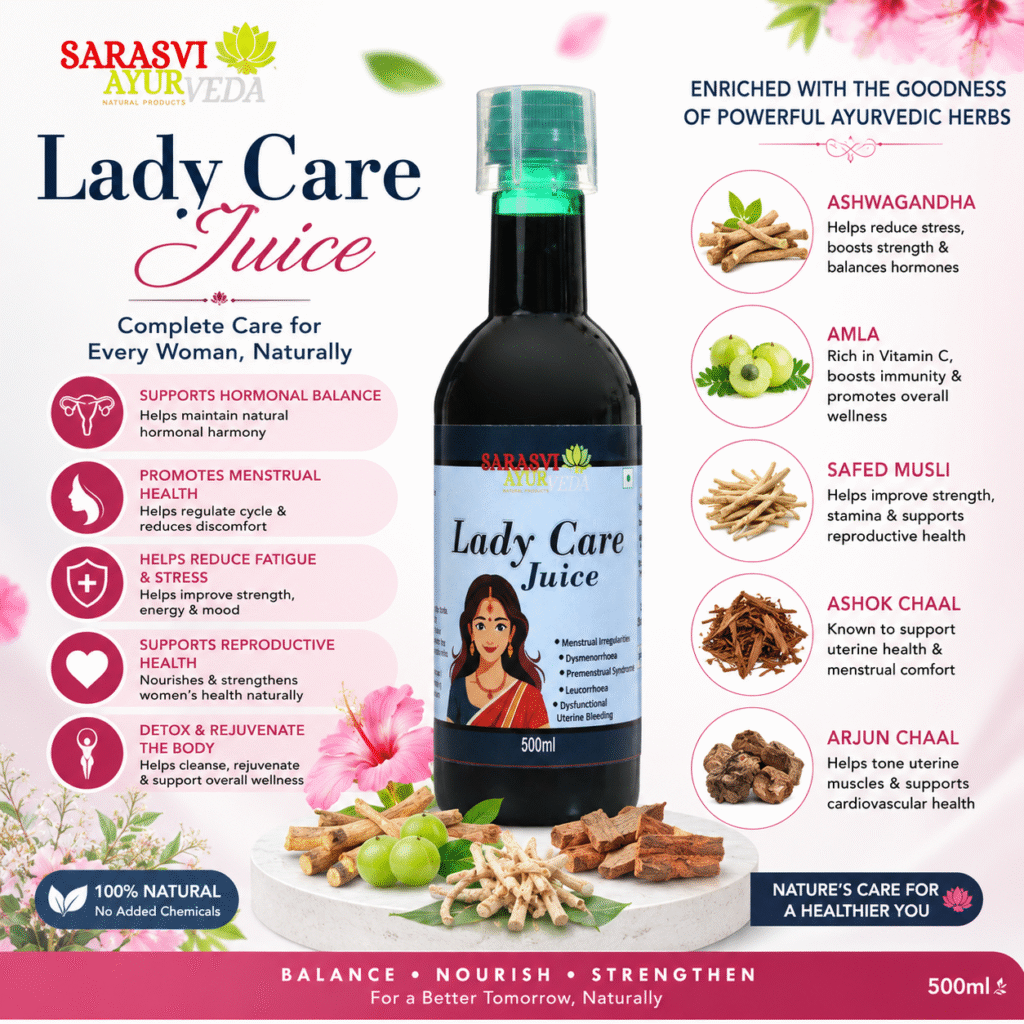

What is Lady Care Juice?